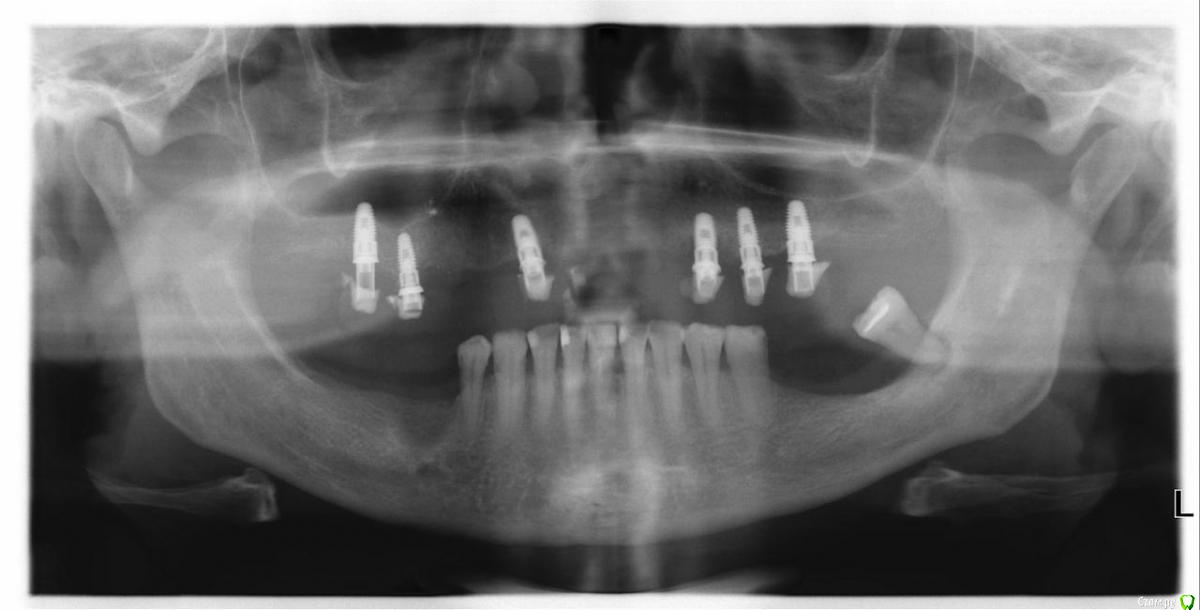

Dr.Stomatolog Опубликовано 21 мая, 2019 Автор Поделиться Опубликовано 21 мая, 2019 Для любителей снимков. Есть и КТ. Давайте только по делу, что и как все знают. Мне бы про РЕНОВК информации. Есть ещё другие уже отпротезированные. Ссылка на комментарий

Dr.Stomatolog Опубликовано 21 мая, 2019 Автор Поделиться Опубликовано 21 мая, 2019 Вопрос есть ли менеджеры торгующие запчастями. И какой трансфер и аналог идёт для импланта с шестигранником 2,2. Похожи ли данные импланты на ренова. Ссылка на комментарий

stommm Опубликовано 22 мая, 2019 Поделиться Опубликовано 22 мая, 2019 Если бы сам знал как решить тогда не спрашивал. Может есть кто работал и работает на этой системе.Не знаю ренова или нет, но Вы возьмёте эти импланты на протезирование? Резорбция уже у многих имплантов, проблемы будут... Ссылка на комментарий

Dr.Stomatolog Опубликовано 22 мая, 2019 Автор Поделиться Опубликовано 22 мая, 2019 Не знаю ренова или нет, но Вы возьмёте эти импланты на протезирование? Резорбция уже у многих имплантов, проблемы будут...От этой работы я сразу отмахнулся, я бы один . Есть ещё ещё пациенты там чуть лучше, и переставлять не хотят. А так я даже не могу понять почему так плохо всё. Ссылка на комментарий